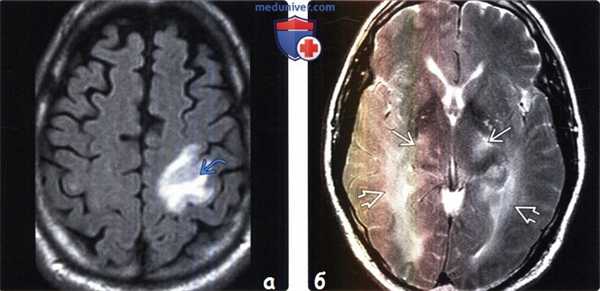

(а) МРТ, FLAIR, аксиальный срез: у пациента с героиновой зависимостью (использовался внутривенный способ введения), который поступил в лечебное учреждение с правосторонним гемипарезом в области левой прецентральной извилины определяется зона инфаркта. В данной области наблюдалось ограничение диффузии (изображения не представлены). Ишемия является наиболее частым острым нейрососудистым осложнением употребления героина.

(б) МРТ, Т2-ВИ: у пациента в коматозном состоянии, который выпивал галлон водки или виски ежедневно на протяжении целой недели определяется диффузный отек головного мозга, повышение интенсивности сигнала от белого вещества и поражение таламусов, что указывает на острое алкогольное отравление.